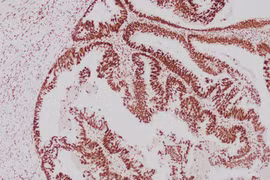

Ung thư đồng phát ở dạ dày - đại tràng, dấu hiệu ít ngờ tới

Cơn đau bụng thoáng qua có thể là dấu hiệu của ung thư hiếm gặp ở hai cơ quan tiêu hóa quan trọng, cần kiểm tra định kỳ để phát hiện sớm.